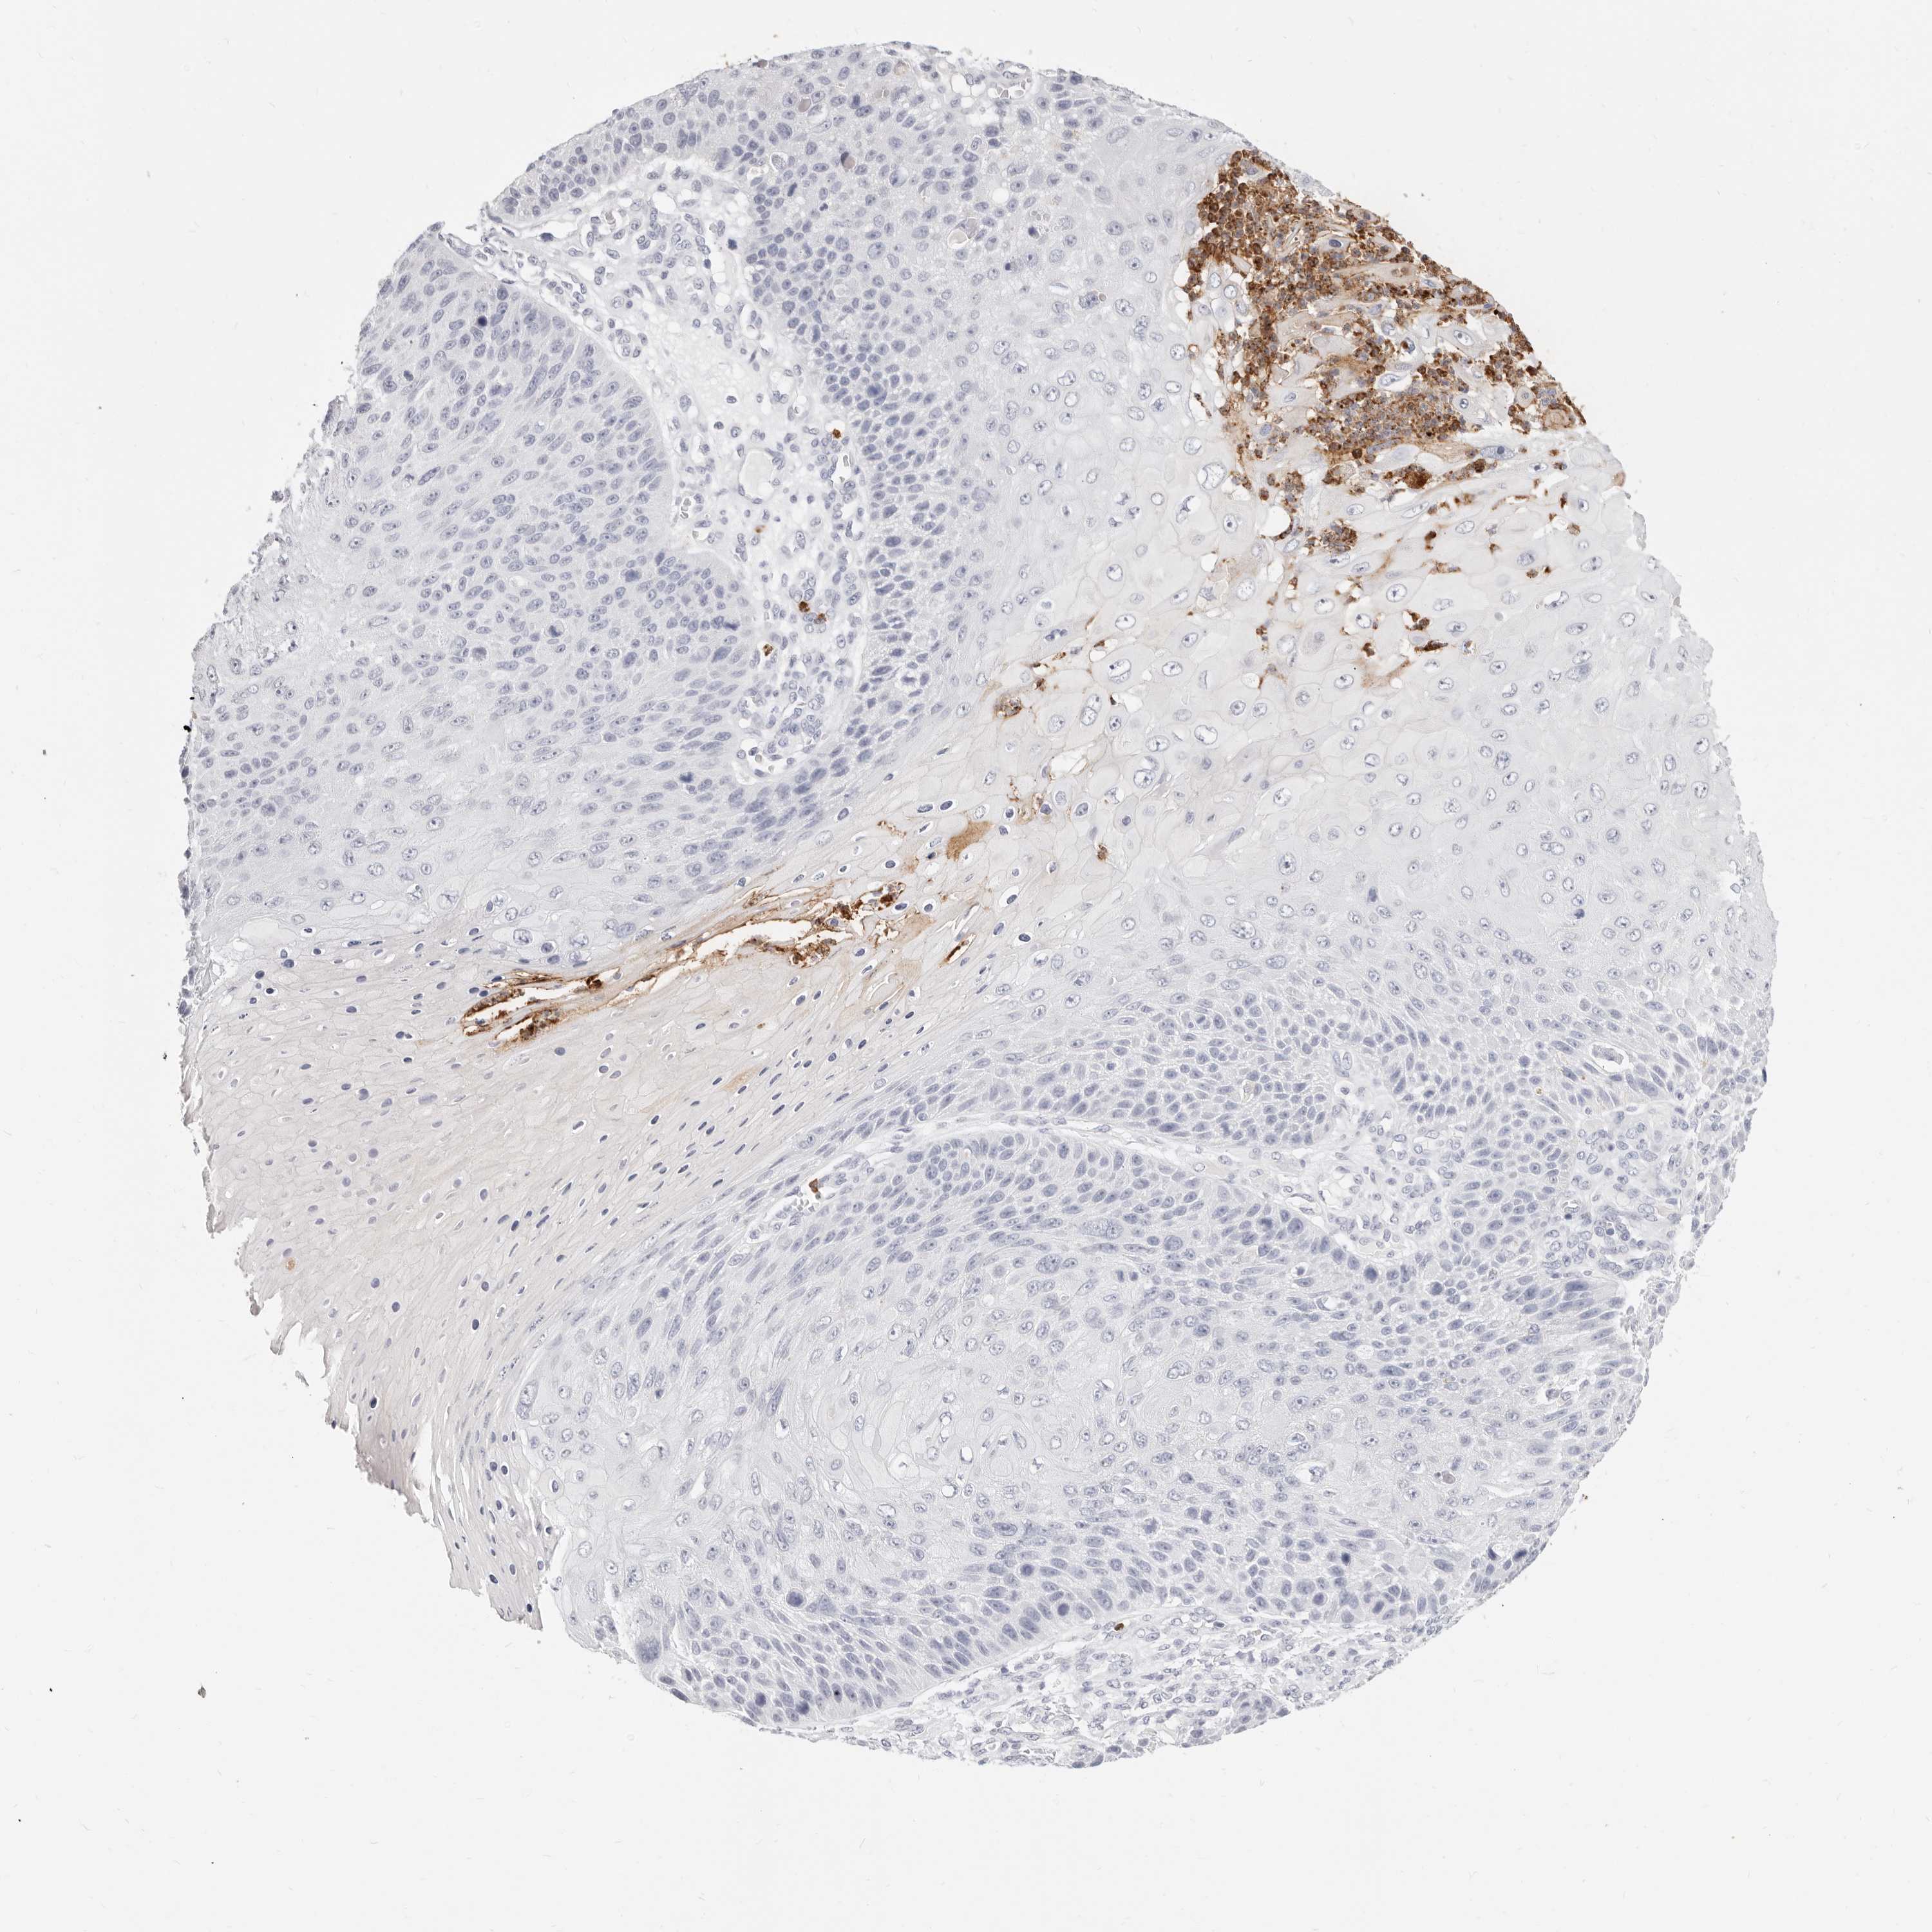

SKIN CANCER - Protein expressioni

A mouse-over function shows sample information and annotation data. Click on an image to view it in a full screen mode. Samples can be filtered based on level of antibody staining by selecting one or several of the following categories: high, medium, low and not detected. The assay and annotation is described here.

Antibody staining in the annotated cell types in the current human tissue is reported as not detected, low, medium, or high, based on conventional immunohistochemistry profiling in selected tissues. This score is based on the combination of the staining intensity and fraction of stained cells.

Each image is clickable and will lead to virtual microscopy that enables deeper exploration of all samples and also displays staining intensity scores, fraction scores and subcellular localization as well as patient and tissue information for each sample.

Squamous cell carcinoma, NOS